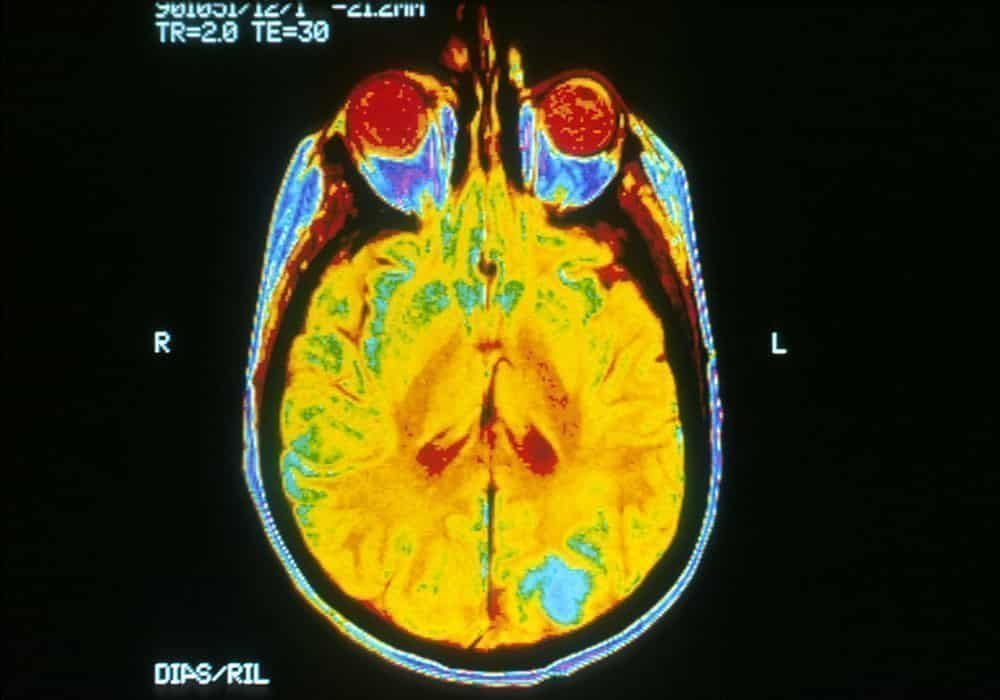

- Tes diagnostik untuk kanker otak melibatkan riwayat, pemeriksaan fisik, dan biasanya prosedur pencitraan otak CT atau MRI; terkadang biopsi jaringan otak dilakukan.